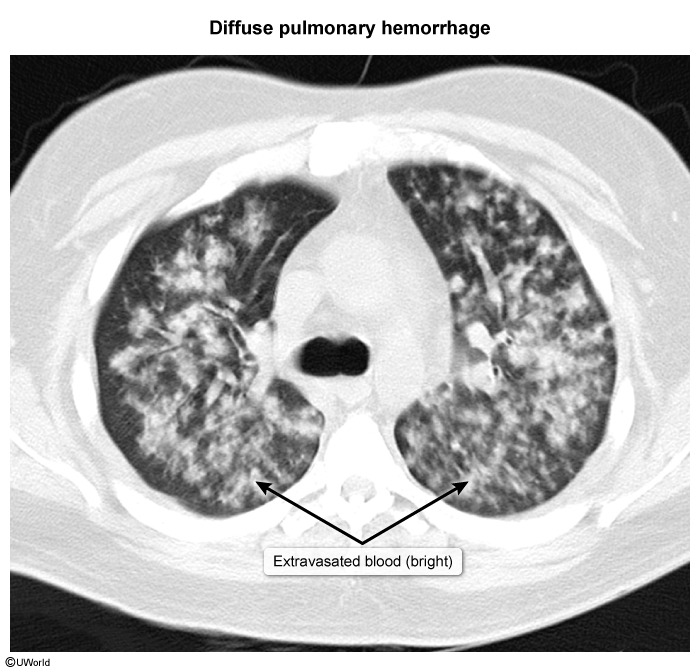

Widespread capillary inflammation can cause diffuse alveolar hemorrhage (DAH), which appears as bilateral alveolar opacification (

image 4

Symptoms include chest pain, dyspnea, hypoxemia, and hemoptysis, which can sometimes be life-threatening (eg, erosion into bronchial artery).